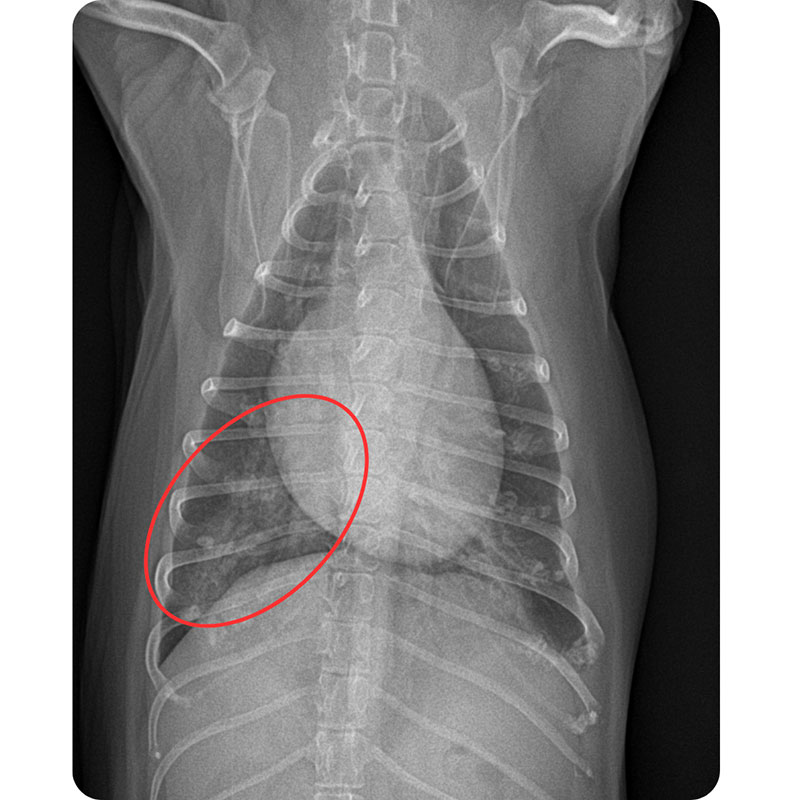

胸部X線検査

肺野に見られる浸潤影、気管支壁の肥厚、区域性の肺不透過像などを確認します。典型的な誤嚥性肺炎では、右中肺葉の異常がよく見られます。